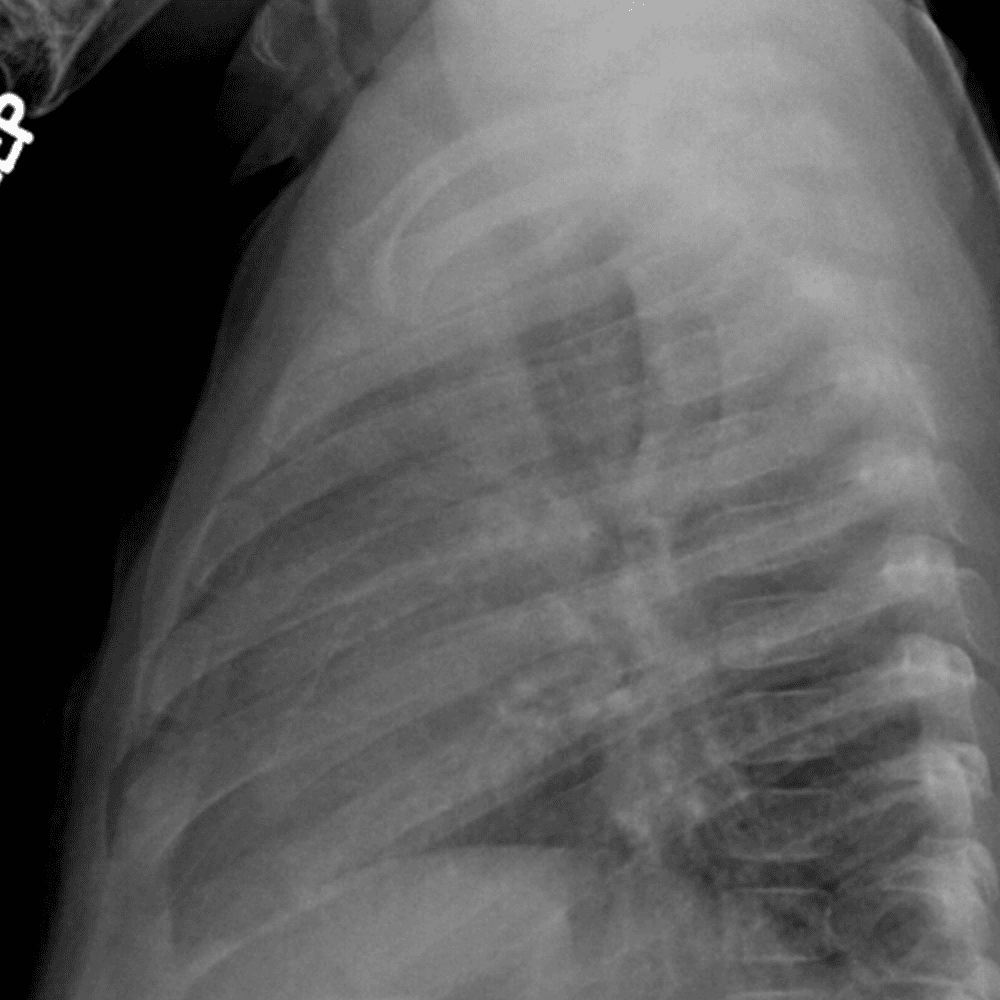

Peds Chest

Practice

Simulates call by including subtle or difficult cases and some normals.

50 cases